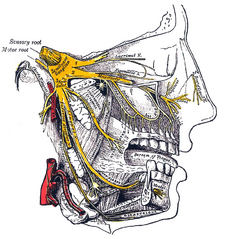

The sensations registered by the human nose derive from the first two branches of the trigeminal nerve (cranial nerve V). The nerve listings indicate the respective innervation (sensory distribution) of the trigeminal nerve branches within the nose, the face, and the upper jaw (maxilla).

- The maxillary division innervation

- Maxillary nerve – conveys sensation to the upper jaw and the face.

- Infraorbital nerve – conveys sensation to the area from below the eye socket to the external nares (nostrils).

- Zygomatic nerve – through the zygomatic bone and the zygomatic arch, conveys sensation to the cheekbone areas.

- Superior posterior dental nerve – sensation in the teeth and the gums.

- Superior anterior dental nerve – mediates the sneeze reflex.

- Sphenopalatine nerve – divides into the lateral branch and the septal branch, and conveys sensation from the rear and the central regions of the nasal cavity.

The supply of parasympathetic nerves to the face and the upper jaw (maxilla) derives from the greater superficial petrosal (GSP) branch of cranial nerve VII, the facial nerve. The GSP nerve joins the deep petrosal nerve (of the sympathetic nervous system), derived from the carotid plexus, to form the vidian nerve (in the vidian canal) that traverses the pterygopalatine ganglion (an autonomic ganglion of the maxillary nerve), wherein only the parasympathetic nerves form synapses, which serve the lacrimal gland and the glands of the nose and of the palate, via the (upper jaw) maxillary division of cranial nerve V, the trigeminal nerve.